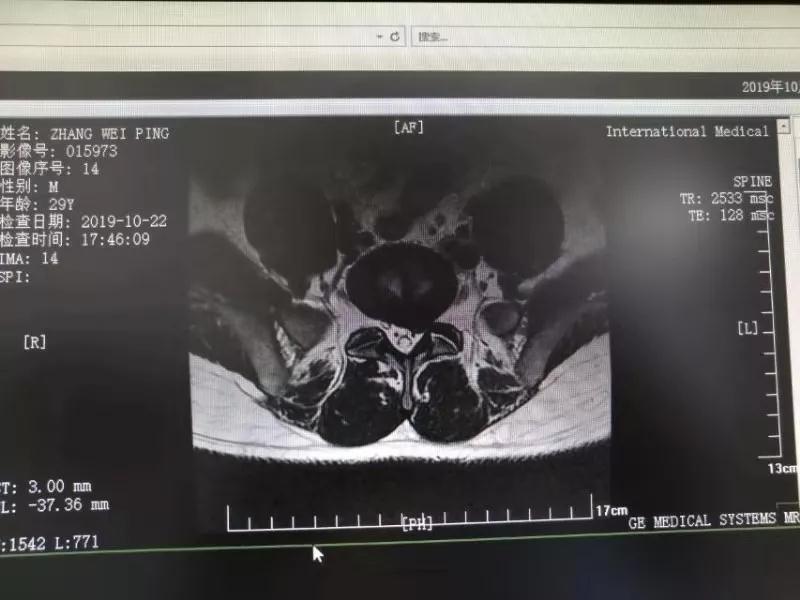

10月25日,29歲的患者小張了解到西安國(guó)際醫(yī)學(xué)中心骨科醫(yī)院專(zhuān)家云集,一大早便在家人的陪同下,來(lái)到西安國(guó)際醫(yī)學(xué)中心骨科醫(yī)院就診?!拔已闯掷m(xù)2年多,最近感冒后腰痛癥狀明顯加重了。”小張面露苦楚,因?yàn)殚L(zhǎng)期腰痛、左下肢放射性疼痛,她晚上睡覺(jué)不能平躺,經(jīng)常疼得睡不著,需要口服止痛藥物才能有所緩解。走路走不了多遠(yuǎn)就開(kāi)始腿抽的疼,嚴(yán)重影響到工作和生活。

結(jié)合患者的檢查以及年齡情況,王自立副院長(zhǎng)推薦讓專(zhuān)門(mén)研究椎間孔鏡技術(shù)王雄勛主任給小張做微創(chuàng)的椎間孔鏡手術(shù)。該手術(shù)創(chuàng)傷很小,不影響脊柱的穩(wěn)定性,尤其適合于椎間盤(pán)突出的年輕患者,懷著對(duì)骨科醫(yī)院專(zhuān)家的信任,小張與家人商議后,接受手術(shù)治療。